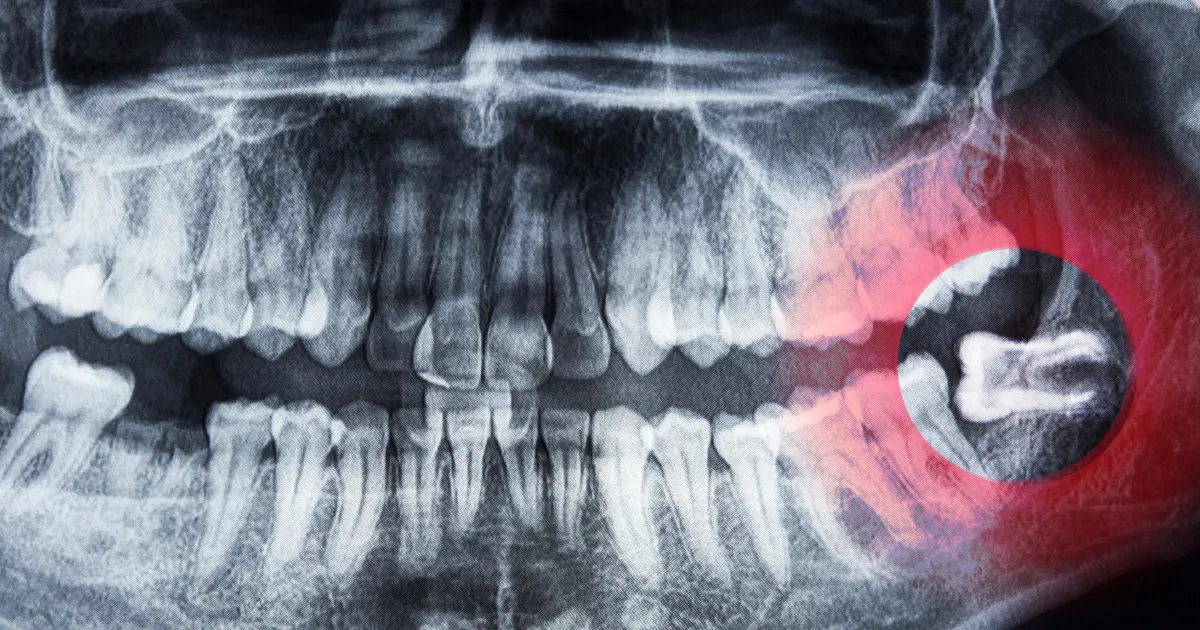

親知らずの深さ

想像すると怖そうですが、、、歯が深く埋まっているほど、抜歯に時間がかかりやすいです。CTスキャン(立体画像)による事前の精密検査が必要です。

下顎管との近さ

下顎管(下歯槽神経)が近い場合、神経損傷のリスクがあるため慎重な対応が求められます。

こちらも上記と同じくCT撮影により事前の精密検査と同意書が必要となります。